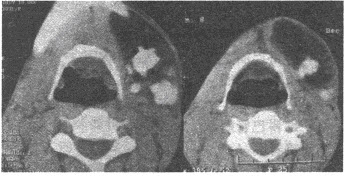

男,22岁,半年前无意中发现左颌下肿物。CT表现如图所示,最可能诊断为()

A:脂肪瘤

B:脂肪肉瘤

C:畸胎瘤

D:淋巴管瘤

E:血管瘤